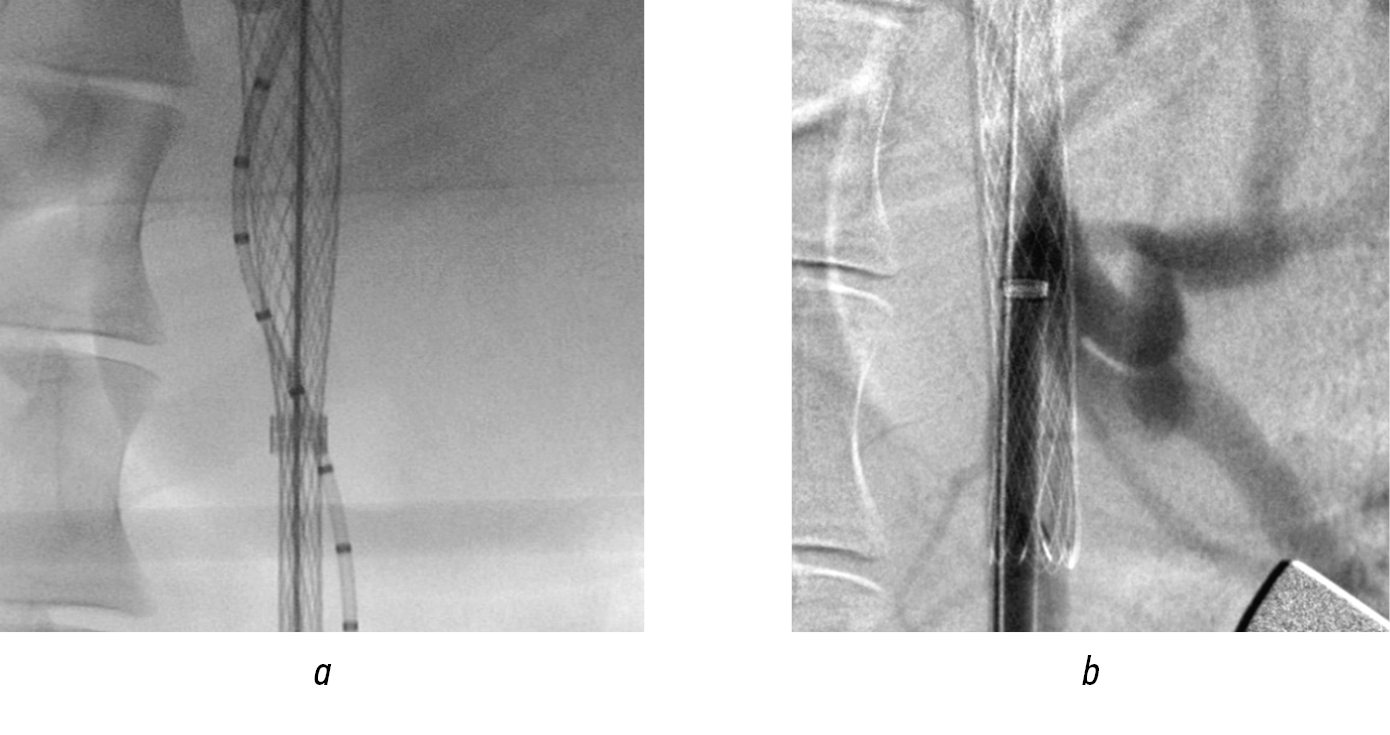

Alternately, personalized fenestration of the graft wall was performed in the projection of the orifices of the celiac trunk and superior mesenteric artery. Balloon dilatation of the fenestrated openings was subsequently performed with the implantation of lead modules into the visceral branches (Figs. 15 and 16). After their installation, dilatation with a balloon catheter was mandatory. In the control image, the structure was passable, and the visceral branches were clearly contrasted without signs of residual stenosis in the fenestrated area (Fig. 17).

Fig. 15. Branching of the ventral trunk mouth: а — personalized fenestration over the ventral trunk mouth; b — balloon dilatation of fenestration; c — implantation of visceral branching

Fig. 16. Stages of endoprosthetics in the suprarenal aorta (continued): а — personalized fenestration over the mouth of the superior mesenteric artery; b — balloon dilation of the fenestration opening; c — implantation of the module into the superior mesenteric artery

Fig. 17. Angiograms after prosthetics of visceral branches: a — control after implantation; b — post-dilation of modules; c — control snapshot

All animals survived, and no neurological disorders developed. No problems associated with impaired visceral circulation were recorded. The follow-up of the operated animals lasted 21 days, after which they were sacrificed, and necropsy material was obtained. All structures were passable, and the walls of the grafts were impermeable to liquids, including blood (Fig. 18).

Fig. 18. Sectional material 21 days after implantation: a — main part and the lead module; b — fenestration zone of the graft wall; c — lead module